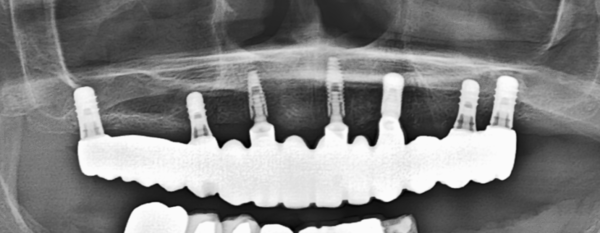

●下顎の場合、神経を回避してインプラント埋入ができる

神経がこのようにループしていますので、ガイドなしでは危険です。

ガイドシステムを利用しなくても、正確に問題なく埋入できています。(すべてネジ止め固定)